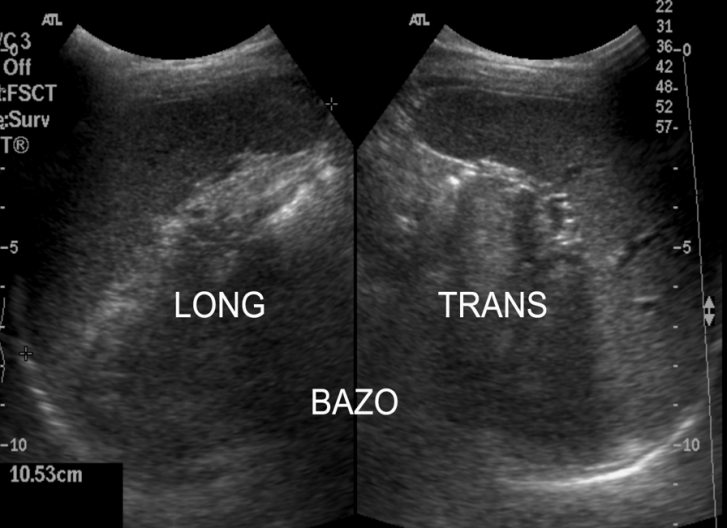

Partiremos de la posición en longitudinal en línea axilar media izquierda a la altura de la 9-10 costilla y ahí buscaremos el órgano según anatomías. Hacemos cortes transverso y longitudinal.

Punto de partida. Corte Longitudinal.

Cortes.Posiciones de Sonda.

Ecográficamente es una estructura voluminosa, hiperecogénica y homogénea que no debe medir en adultos más de 12 cms. Los vasos de la estructura se verán anecoicos.

Semiología ecográfica.

Detalle del vaso.

El objetivo principalmente es observar el órgano, demostrar que no tenga patología y hacerle medidas en el corte longitudinal al menos.

Longitudinal con medidas. Observe el lector el pictograma.

Transverso. Detalle del pictograma en amarillo.

El o la paciente se debe encontrar en decúbito supino o decúbito lateral derecho, recomiendo exploración del órgano en ambas posiciones y escoger la mejor para hacer las fotos y medidas.

La estructura del Bazo hace que tanto en transverso como en longitudinal el Bazo aparece ecográficamente como una estructura que estuviese reflejada en un espejo. Mira:

En Long y en Trans como si la estructura estuviese reflejada.